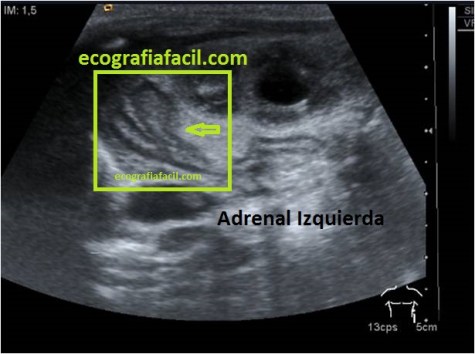

La imagen es un corte sagital realizada con sonda convex de baja frecuencia, estamos usando 6 mHz con armónicos, ganancia general de 86 y un rango dinámico de 65, es decir un valor medio. El pictograma indica la posición en decúbito supino y corte sagital.El preset es de ecografía de Abdomen General.La profundidad de estudio es de 12 cms. El foco está situado en torno a los 6 cms.

Anatómicamente tenemos una imagen donde observamos la relación hepatorrenal, donde ambos órganos son isoecogénicos.Entre ambos existe una línea de separación fina e hiperecogénica, corresponde al Espacio de Morrison, lugar de depósito de líquido ascítico habitual.

En el Hígado llama la atención una estructura hiperecogénica y homogénea, ligéramente redondeada,en el plano anteroposterior mide en torno a 2,5 cms y corresponde con un hemangioma típico.

El Riñón es de un aspecto normal, la corteza en hipoecogénica, el seno renal, hiperecogénico, no está dilatado, mide algo más de 9 cms, su ecoarquitectura es correcta, no tiene ni masas ni imágenes que sugieran litiasis.

Riñón derecho e hígado comparten una región en la imagen, es la que corresponde al polo superior del riñón y a la porción más caudal y externa del hígado, es la zona de la Suprarrenal derecha, lugar que debemos encontrar libre a partir del año de vida, es decir, no debemos ver dicha suprarrenal ni tampoco ninguna LOE a ese nivel.

A nivel del polo inferior del Riñón, superficial, observamos una imagen hiperecogénica, curva, con una llamativa sombra acústica posterior que corresponde con gas intestinal correspondiente a la tercera porción del duodeno, el gas es el culpable de esta ausencia de información que se traduce en un artefacto típico del gas intestinal.

La flecha negra está marcando el Músculo Psoas, que «acuna» al riñón derecho.

The image is a sagittal cut made with a low frequency convex probe, we are using 6 mHz with harmonics, a general gain of 86 and a dynamic range of 65, that is, an average value. The pictogram indicates the position in supine decubitus and sagittal section. The preset is a General Abdomen ultrasound. The study depth is 12 cm. The focus is around 6 cm.

Anatomically we have an image where we observe the hepatorenal relationship, where both organs are isoechogenic. Between both there is a thin and hyperechogenic separation line, corresponds to the Morrison Space, place of habitual ascitic fluid deposition.

In the Liver, a hyperechogenic and homogeneous structure, slightly rounded, is noticeable in the anteroposterior plane, measuring around 2.5 cms and corresponds to a typical hemangioma.

The Kidney is of a normal appearance, the cortex is hypoechoic, the renal sinus is hyperechogenic, it is not dilated, it measures a little more than 9 cm, its eco-architecture is correct, it does not have masses or images suggestive of lithiasis.

Right kidney and liver share a region in the image, it is the one that corresponds to the upper pole of the kidney and to the most caudal and external portion of the liver, it is the right adrenal zone, a place that we should find free from the year of life, that is to say, we should not see adrenal gossip nor any LOE at that level.

At the level of the lower pole of the kidney, superficial, we observed a hyperechoic, curved image, with a striking posterior acoustic shadow that corresponds to intestinal gas corresponding to the third portion of the duodenum, the gas is the culprit of this lack of information that translates into a typical artifact of intestinal gas.

The black arrow is marking the Psoas Muscle, which «cradles» the right kidney.